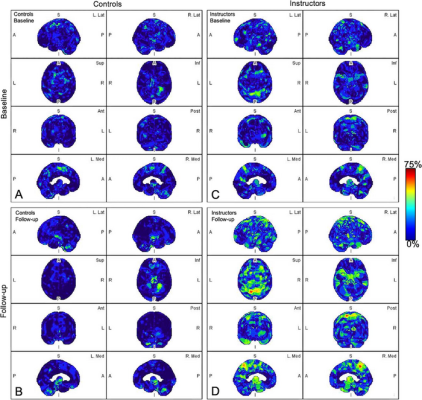

Parametric maps of amyloid deposition in healthy control participants (A and B) and blast-exposed military instructors (C and D) at baseline (A and C) and follow-up (B and D). The blue-to-red scale indicates the frequency of statistically abnormal amyloid uptake in a particular brain voxel. Whereas no abnormal amyloid uptake was identified at baseline or follow-up in healthy control participants (A, B), amyloid deposition occurred most frequently in blast-exposed participants in the superior parietal lobules, precuneus, cingulum, paracentral lobules, and anterior temporal and occipital lobes (D). A = anterior, Ant = anterior, I = inferior, Inf = inferior, L = left, Lat = lateral, Med = medial, P = posterior, Post = posterior, R = right, S = superior, Sup = superior. Image courtesy of RSNA.

All participants underwent a PET scan of the head to evaluate and quantify amyloid changes. Analysis software was used to segment six brain regions that are usually associated with Alzheimer’s disease and TBI.

Abnormal amyloid accumulation was seen in six of the nine participants who were exposed to explosions. Three of the participants had one region of the brain with increased amyloid accumulation, two participants had two regions, and one participant had three regions with abnormal accumulation.

None of the healthy control participants showed any abnormal amyloid accumulation.